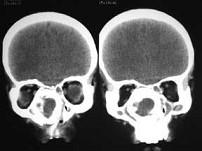

女,14岁,渐进性鼻塞2年余,右眼肿痛数月,CT如图所示,应诊断为 ( )

• A.筛骨骨化性纤维瘤

• B.筛骨骨肉瘤

• C.筛骨结核

• D.筛骨软骨瘤

• E.筛骨骨纤维瘤

答案: A